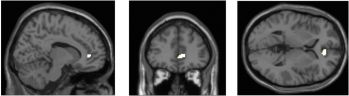

TL;DR this more physical study found lower grey matter density in areas of the brain that handle empathy, emotional control and cognitive control, and higher levels of stress & short term memory loss in serial multitaskers.